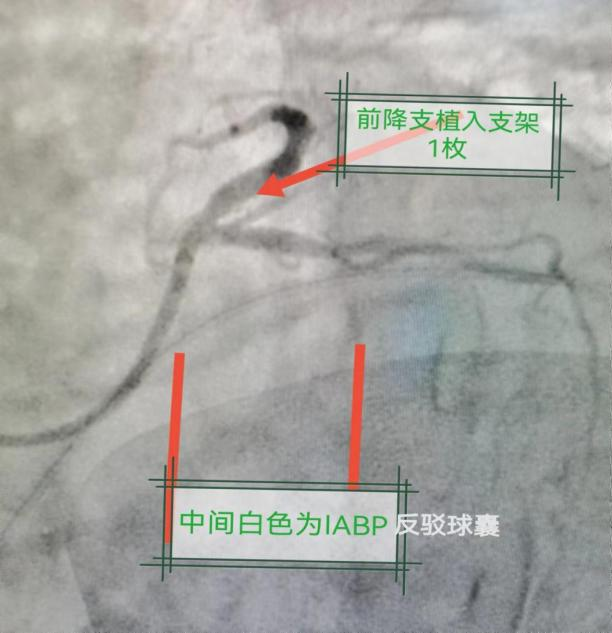

行冠状动脉造影:冠脉右优势型,LAD开口闭塞,LCX近中段60%狭窄,向右冠脉提供逆灌,反复尝试共用管不能到达右冠脉开口,更换JR4.0造影导管,仍不能到达右冠脉开口,告知患者,择日行CTA检查明确右冠脉情况。在IABP保护下于前降支植入支架2枚,冠脉血流达TIMI3级。药物治疗1周后患者康复出院。

术前

术后